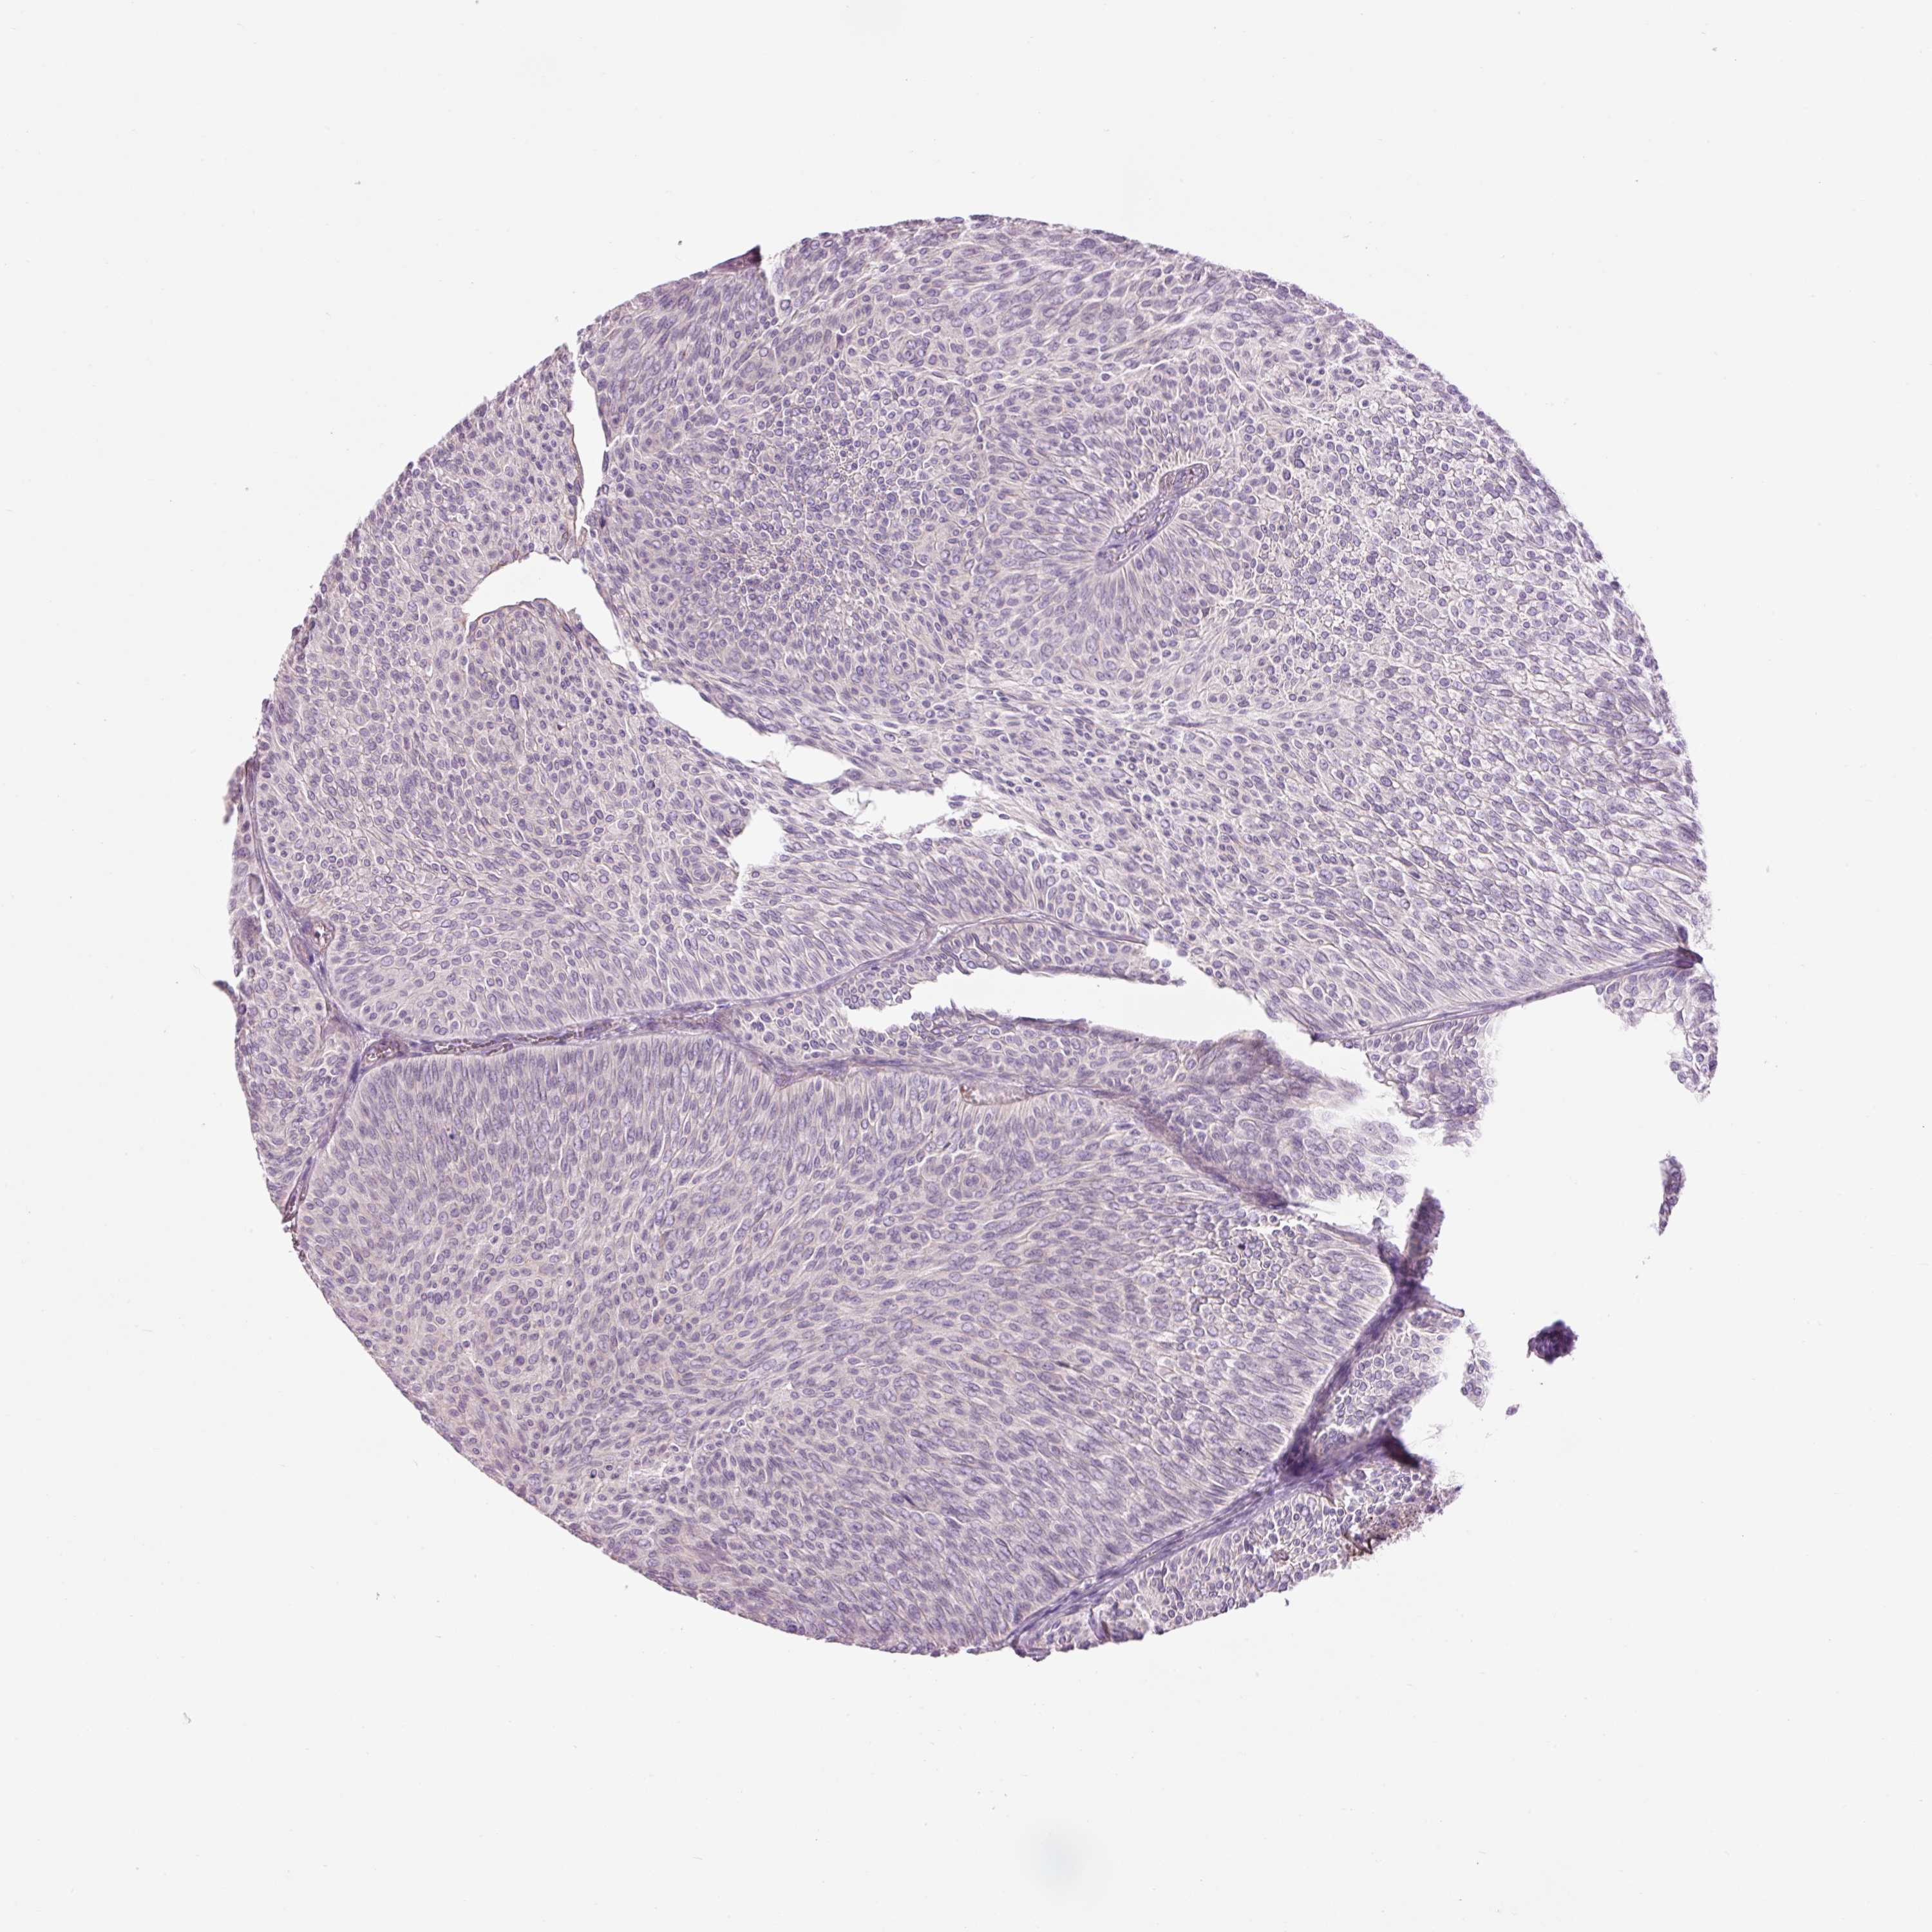

UROTHELIAL CANCER - Protein expressioni

A mouse-over function shows sample information and annotation data. Click on an image to view it in a full screen mode. Samples can be filtered based on level of antibody staining by selecting one or several of the following categories: high, medium, low and not detected. The assay and annotation is described here.

Antibody stainingi

Antibody staining in the annotated cell types in the current human tissue is reported as not detected, low, medium, or high, based on conventional immunohistochemistry profiling in selected tissues. This score is based on the combination of the staining intensity and fraction of stained cells.

Each image is clickable and will lead to virtual microscopy that enables deeper exploration of all samples and also displays staining intensity scores, fraction scores and subcellular localization as well as patient and tissue information for each sample.

Antibody HPA039149

Urothelial carcinoma, High grade

Urothelial carcinoma, NOS

Urothelial carcinoma, Low grade